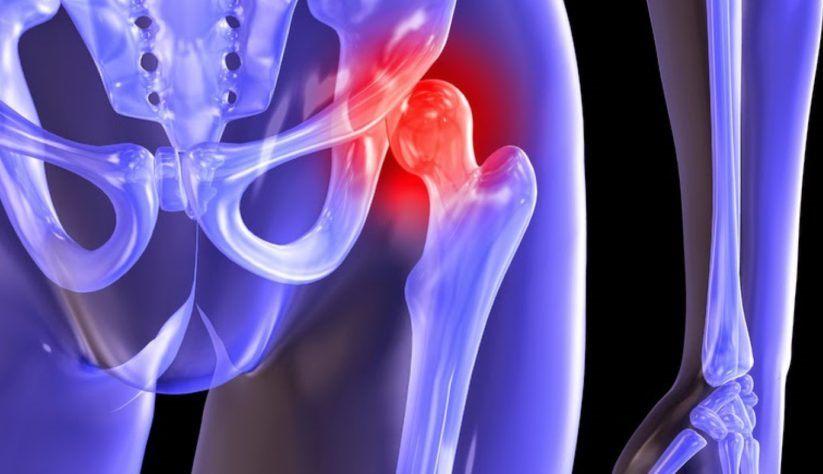

Артрит у детей, особенно воспаление тазобедренного сустава, вызывает серьезные беспокойства у родителей. Многие отмечают, что симптомы могут проявляться неожиданно: ребенок начинает жаловаться на боль в бедре или колене, может хромать или отказываться от активных игр. Врачи подчеркивают важность ранней диагностики, так как запущенные случаи могут привести к серьезным осложнениям. Классификация артритов включает инфекционные, аутоиммунные и реактивные формы, каждая из которых требует индивидуального подхода к лечению. Лечение может варьироваться от противовоспалительных препаратов до физиотерапии и, в некоторых случаях, хирургического вмешательства. Родители должны быть внимательны к изменениям в поведении ребенка и вовремя обращаться за медицинской помощью, чтобы предотвратить прогрессирование заболевания.